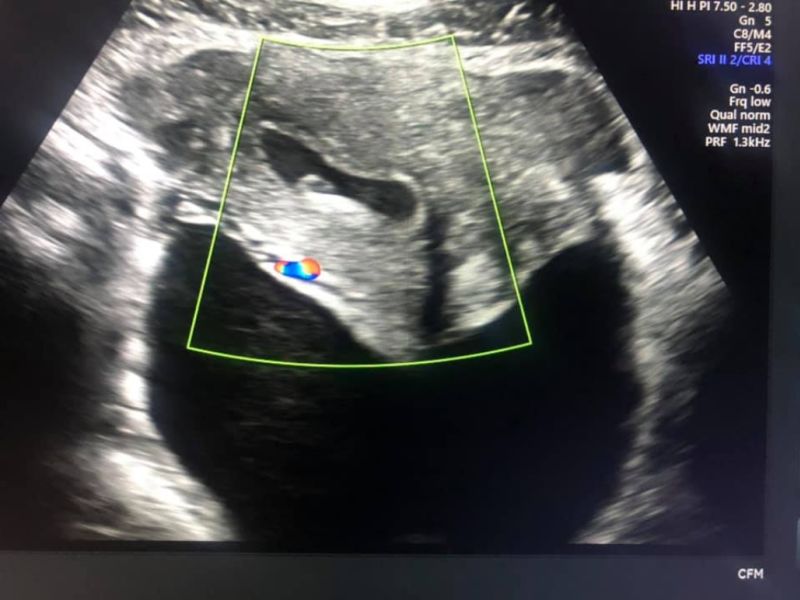

Uterine Rupture

image by: Suyash Sonography Centre

Uterine rupture most likely happens in the late third trimester or during active labor when the uterine wall is at its thinnest...

Uterine rupture is an obstetric emergency, and management is surgical intervention for delivery and uterine repair or hysterectomy. Definitive diagnosis can be made at the time of surgical intervention.

Spontaneous tearing of the uterus. May result in fetus being expelled into peritoneal cavity. Occurs in late pregnancy or active labor.